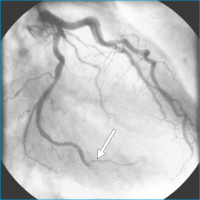

Arteria circumflexa

Abbildung 3: Koronarangiographie: embolischer Verschluß des Ramus marginalis der Arteria circumflexa.